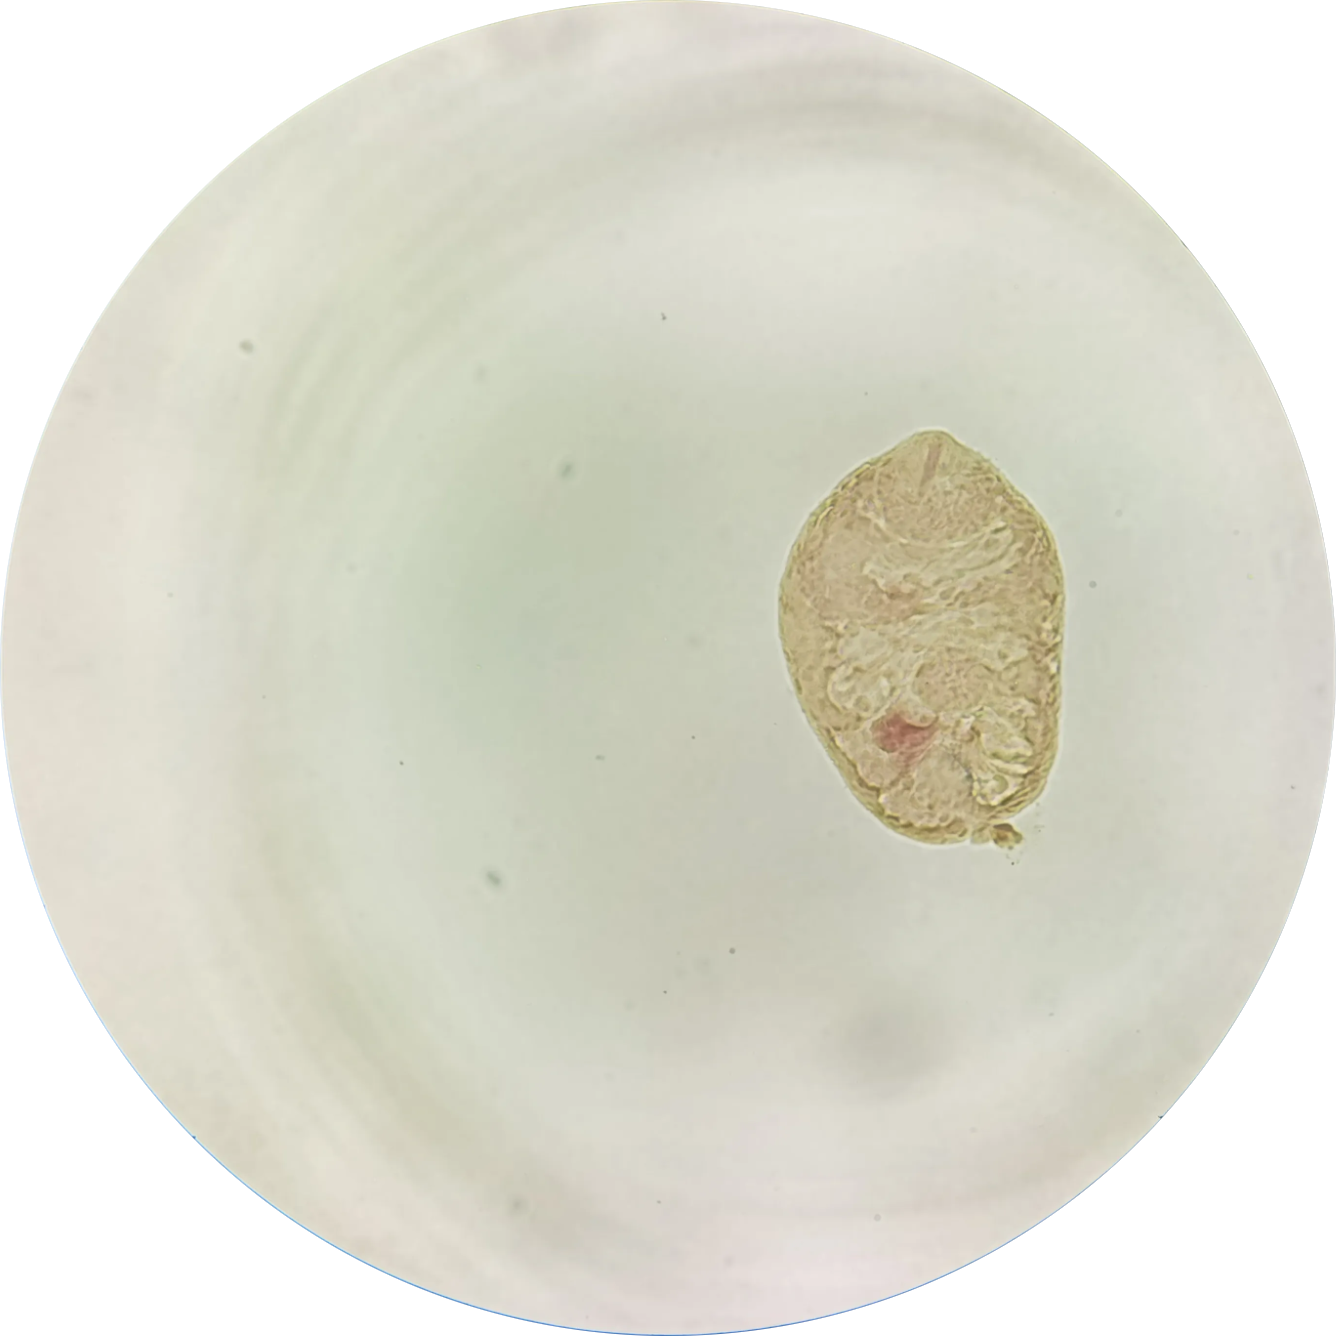

旋毛虫幼虫囊包(肌肉中的螺旋滑梯)